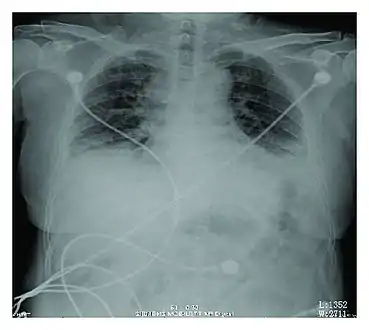

Rapid progression from initial symptoms to respiratory failure is a key feature. An X-ray that shows ARDS is necessary for diagnosis (fluid in the small air sacs (alveoli) in both lungs). In addition, a biopsy of the lung that shows organizing diffuse alveolar damage is required for diagnosis. This type of alveolar damage can be attributed to nonconcentrated and nonlocalized alveoli damage, marked alveolar septal edema with inflammatory cell infiltration, fibroblast proliferation, occasional hyaline membranes, and thickening of the alveolar walls. The septa are lined with atypical, hyperplastic type II pneumocytes, thus leading to the collapse of airspaces. Other diagnostic tests are useful in excluding other similar conditions, but history, X-ray, and biopsy are essential. These other tests may include basic blood work, blood cultures, and bronchoalveolar lavage. The clinical picture is similar to ARDS, but AIP differs from ARDS in that the cause for AIP is not known.

Chest CT images of five persons/cases who developed acute interstitial pneumonia

Acute interstitial pneumonia showing a marked reduction in lung capacity